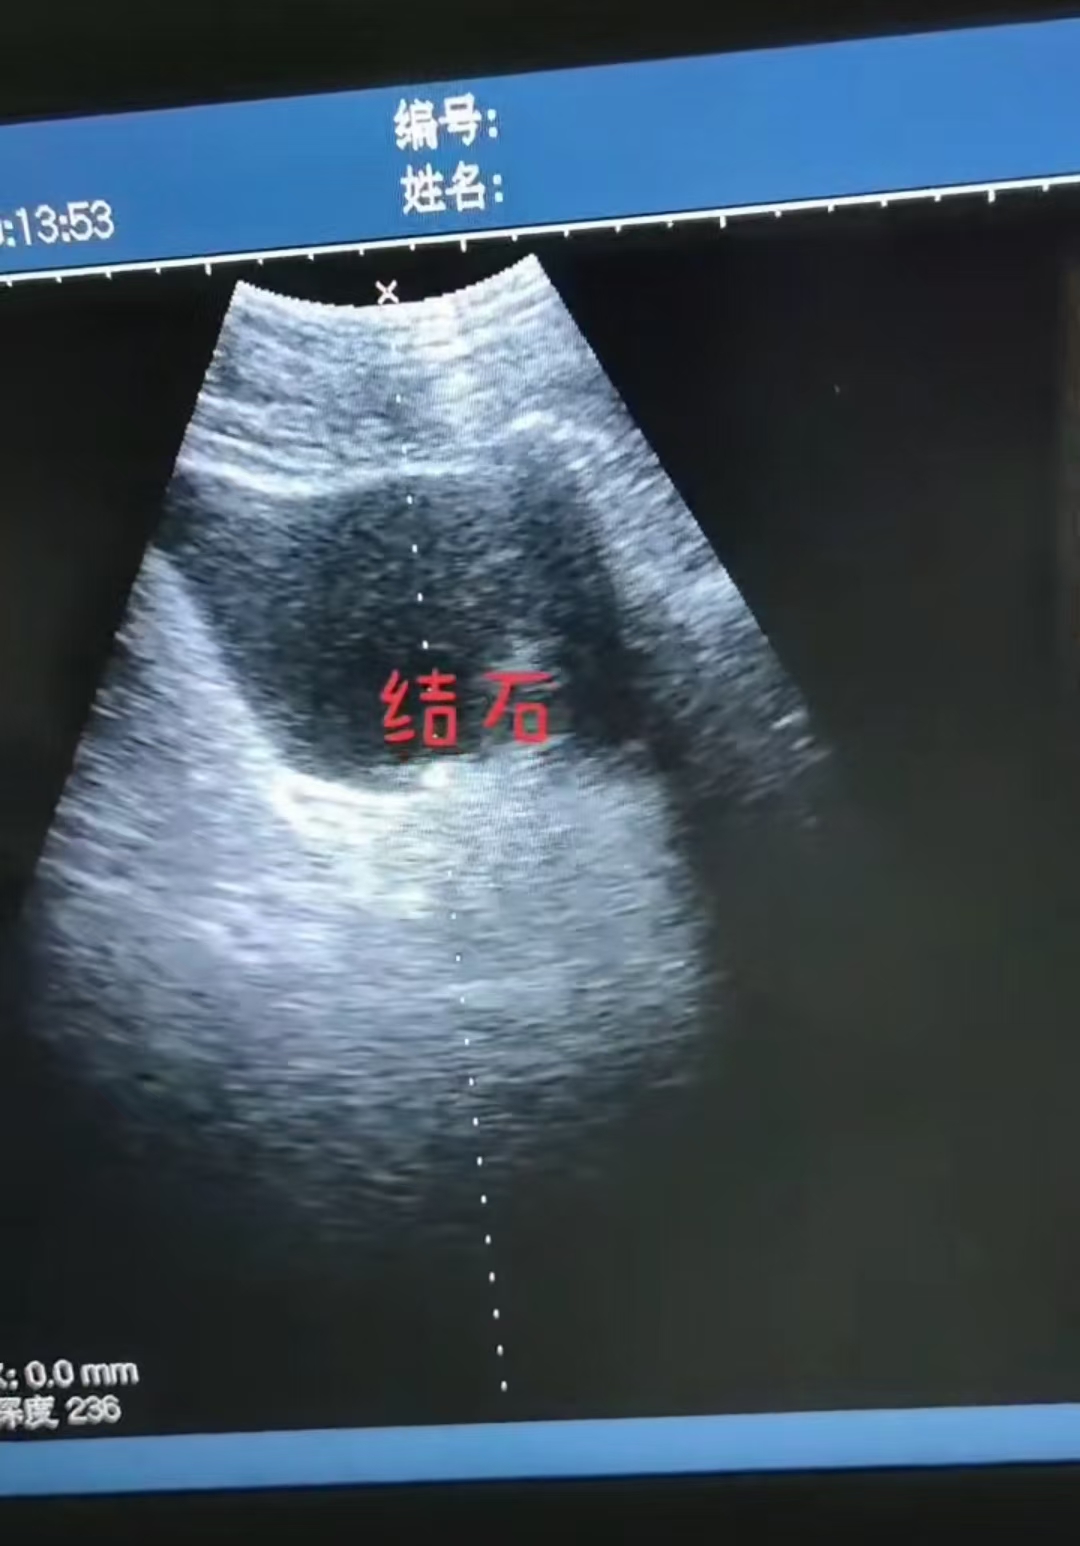

超声如何检查肾结石

肾结石B超检查是通过超声波成像技术观察肾脏结构,识别结石的位置、大小及是否伴有肾积水等并发症。检查时,医生会将探头放置在腰部或腹部,通过声波反射形成的图像判断结石特征,如···...

便携超声对碎石机的应用

便携B超与碎石机配合,核心应用是在泌尿系统结石治疗中实现“实时定位-精准碎石-疗效确认”的闭环操作,尤其适用于门诊、急诊或床旁等移动医疗场景。1. 核心应用场景:泌尿系统···...